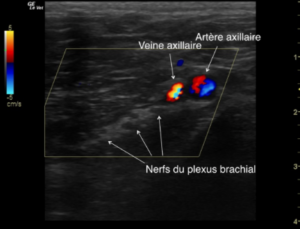

L’animal est en décubitus latéral (ou dorsal), la sonde échographique est placée sur les muscles (superficiel et profond) pectoraux. La première côte et l’artère brachiale servent de référence pour identifier le plexus : les nerfs apparaissent les uns derrière les autres (dans une orientation cranio-caudale), comme des structures rondes hypoéchoiques, entourées d’un tissu hyperéchoique (graisse)

Images échographiques chez le chien (crédit Stephan Mahler) :